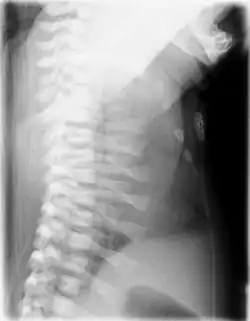

Röntgenbild der Halswirbelsäule seitlich des gleichen Kindes

Die klinische Verdachtsdiagnose wird im Röntgenbild gesichert. Diagnostische Kriterien sind:[1][2][14]

• Kurze, horizontal verlaufende Rippen

• Schmale Beckenschaufeln mit dreizackartiger Begrenzung des Unterrandes, Pfannendach horizontal verlaufend und spornartig nach kaudal weisend

• Vorzeitige Verknöcherung der Femurepiphyse

• Distal betont verkürzte Röhrenknochen

• Zapfenepiphysen der Mittelphalangen